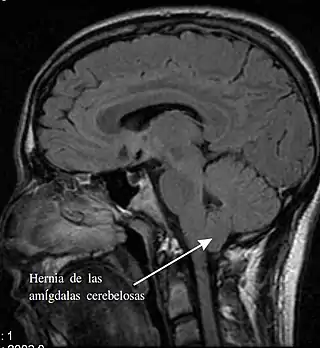

Imagen radiográfica de una persona con malformación de Chiari tipo I. Una parte del cerebelo (amígdala cerebelosa), ha descendido 7 mm por debajo del foramen magno (agujero occipital). | ||

Si las amígdalas cerebelosas son empujadas al canal medular sin involucrar al tallo cerebral, se considera que la Chiari es del tipo I. Afortunadamente,[8] ya que es el tipo más frecuente. Normalmente solo se diagnostica en la adultez, durante un examen dirigido a diagnosticar otras patologías. Todas las Chiari adquiridas o secundarias pertenecen exclusivamente al tipo I.[8]

Las malformaciones de Chiari tipo I pueden, no obstante, obstruir el flujo de líquido cefalorraquídeo y comprimir la médula espinal. Algunas veces están asociadas a la siringomielia.